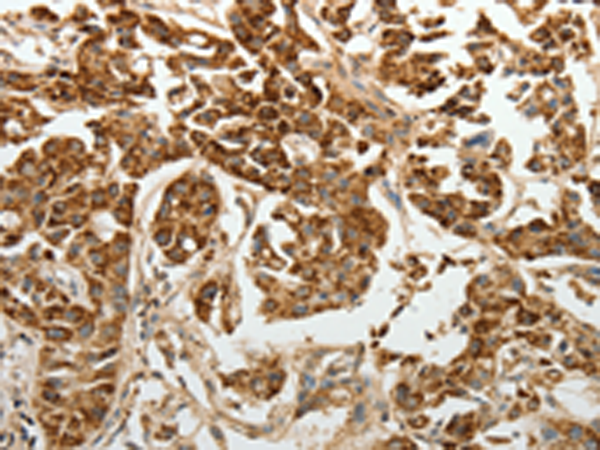

分类: 科研抗体货号: P07572别名: GBF1; GBF-1; PGES2; C9orf15; mPGES-2应用: WB,IHC反应种属: Human, Mouse